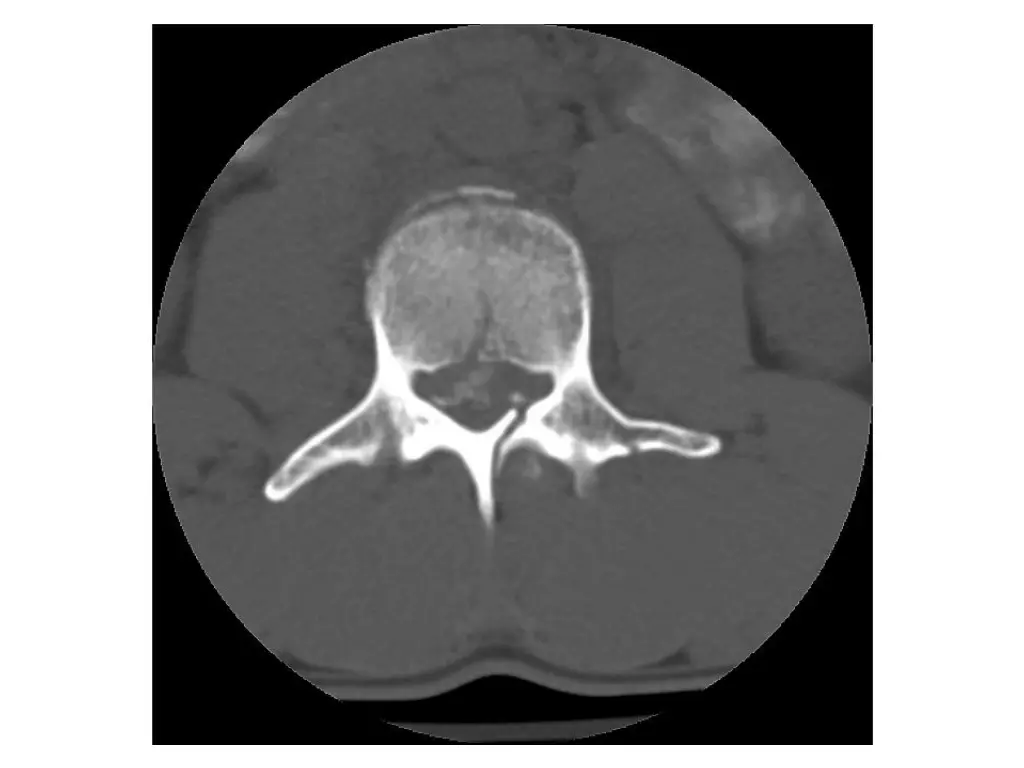

Imaging (Case 1) Midsagittal CT scan Parasagittal CT scan Axial CT scan Midsagittal STIR MRI scan

Imaging (Case 2) Lateral XR Midsagittal CT scan Parasagittal CT scan Axial CT scan